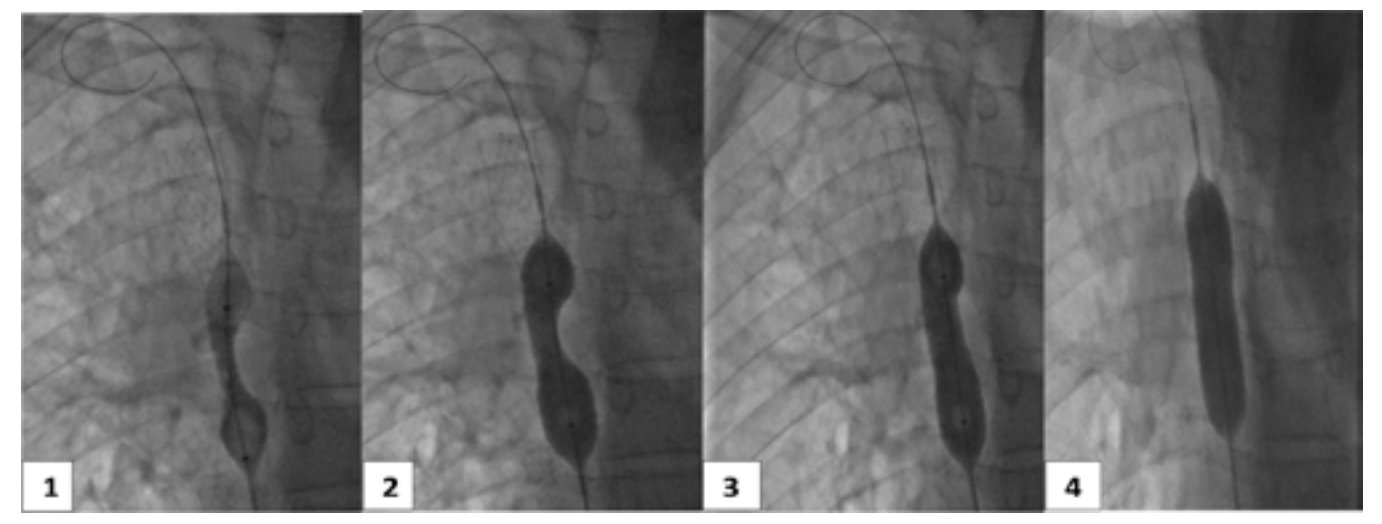

From a therapeutic point of view, endovascular treatment of SVCS had been performed under local anesthesia. Percutaneous vena femoral approach was carried out in 2 cases. Three patients also required the use of the basilica pathway. Before stenting, the caval stenosis was dilated two or three times for almost 10 minutes by means of balloon inflation to the estimated diameter in three cases. We also routinely performed post-stent dilatation. In all procedures, a self-expanding stent had been deployed. The details regarding the stent deployed are summarized in Table 1. As an immediate follow-up, the patients experienced a quick relief of symptoms between 48-72 hours.

Despite technical diversity implemented, we believe that SVCS endovascular treatment should be performed, according to the recommendations of the French Society of CardioVascular Imaging (SFICV).20 In fact, it had to be carried out, firstly, with an undersized caliber balloon, 2 mm smaller than the diameter of the SVC measured. After the deployment of self-expanding stents, inflation should be carried out at low pressure. Many reasons are behind this logic. Firstly, the stent complete expansion will occur spontaneously in the hours or days that follow the procedure, it will avoid hemorrhagic complications due to dissection of the venous wall, rupture or tamponade. In addition to that, the post-inflation corrects the eccentric character and accelerates the self-expansion of the Wallstent. At last, this technique helps to press the thrombus against the endoprosthesis, preventing emboli migration.